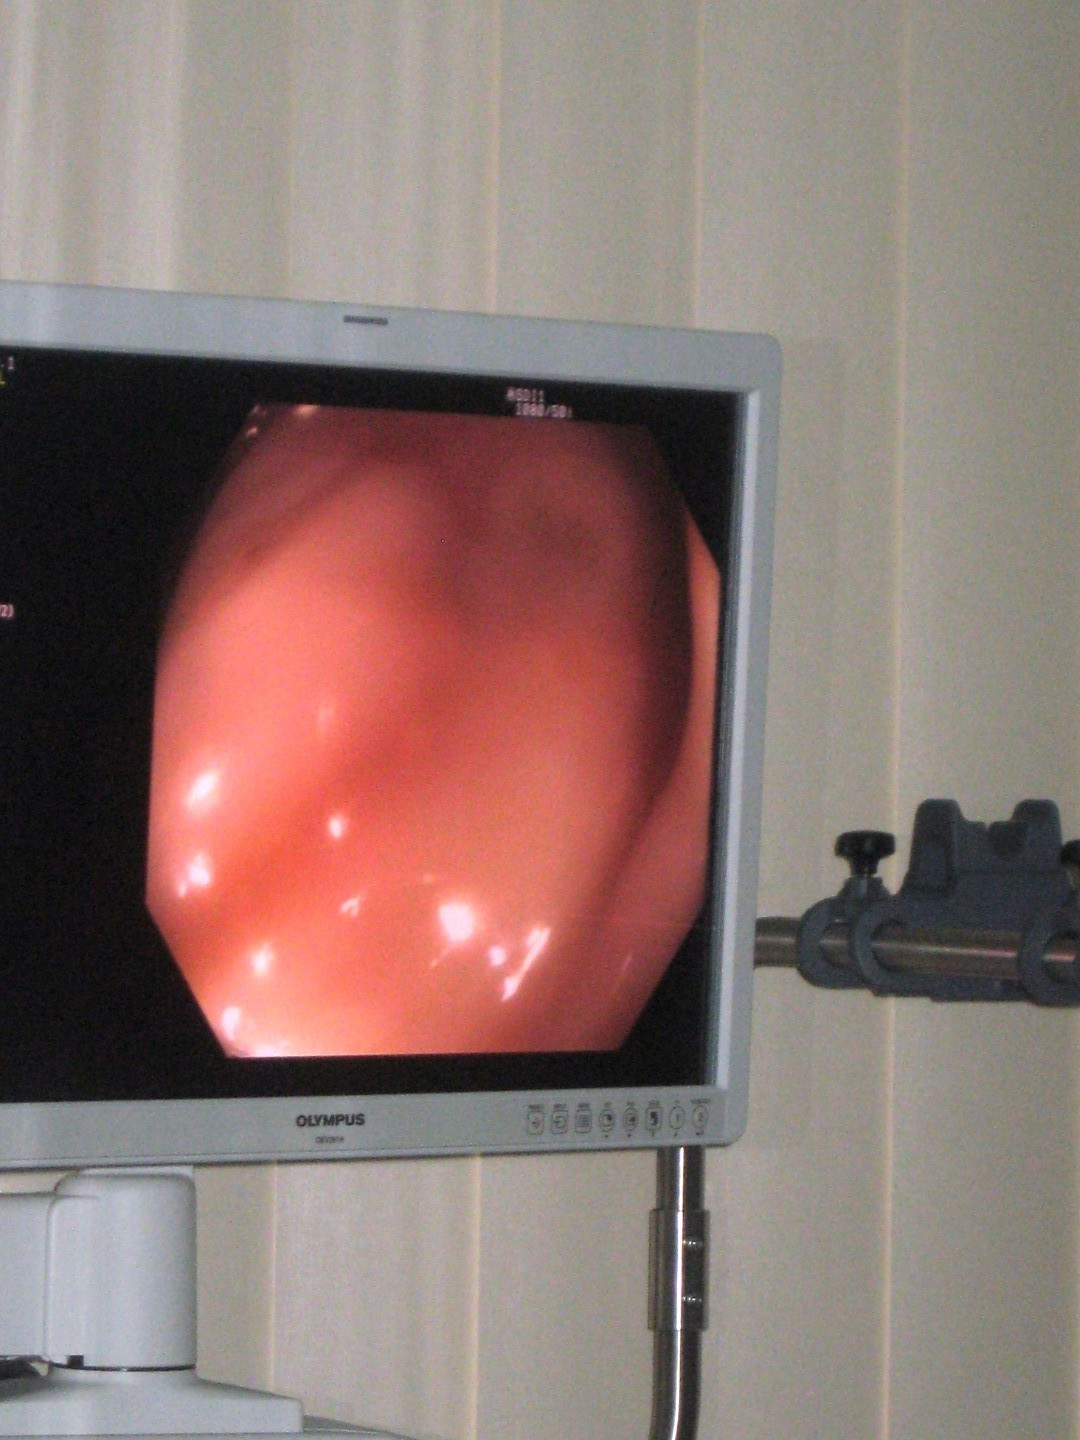

Pacientii din vestul tarii au la dispozitie, incepand de astazi, tehnologie de ultima generatie pentru depistarea leziunilor precanceroase, un aparat endoscopic de mare precizie fiind pus in functiune la Arad.

Aparatul a costat 600.000 de lei, bani asigurati din bugetul Consiliului Judetean, iar cu ajutorul acestuia pot fi localizate cu precizie leziuni cu cativa ani inainte de a deveni canceroase, cand rata de vindecare este de suta la suta.

Sefului Sectiei Gastro-Enterologie a Spitalului Clinic Judetean de Urgenta Arad, Eftimie Miutescu, spune ca noul dispozitiv medical este cel mai performant existent in acest moment in lume, iar in Romania mai exista doua aparate de acest fel, in Targu-Mures si Cluj-Napoca.

Eftimie Miutescu, medic specialist gastro-enterologie: “In 2010, in Arad am introdus, in premiera nationala, imunotestul fecal pentru determinarea hemoragiilor oculte, iar cei care aveau sange microscopic erau supusi colonoscopiei si erau inlaturate leziunile. Acum, aceasta tehnologie noua ne permite sa determinam cu precizie maxima leziunile, fiind cel mai perfromant aparat in acest domeniu. Leziunile sunt depistate inainte de a deveni canceroase”.